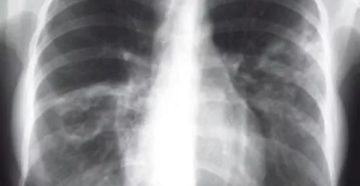

Очаговый туберкулез легких Очаговый туберкулез легких – это форма вторичного туберкулеза, которая протекает с развитием…